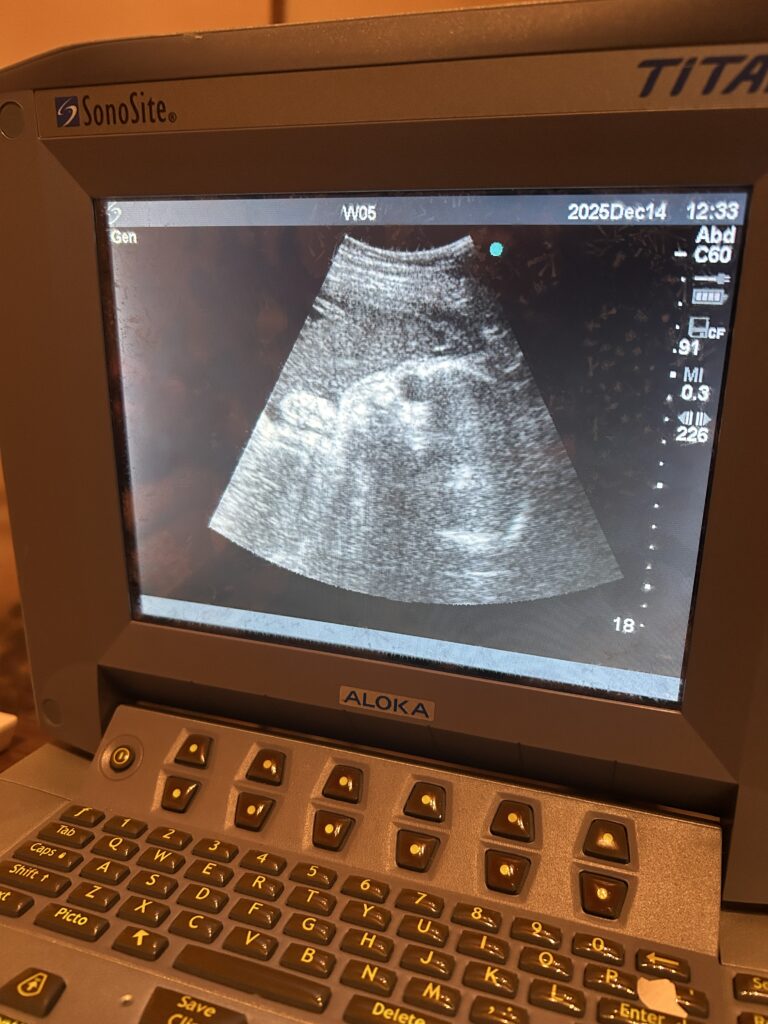

エコーで確認

妊活中から診ている患者さんのエコー! かなり大きくなってきたね! 来年早々に産まれてくるよー! ほぼ毎週見ているこの子も徐々に画面に収まらないくらい大きくなってきて嬉しい限りです! エコーでみてから治療をするので、逆子に […]